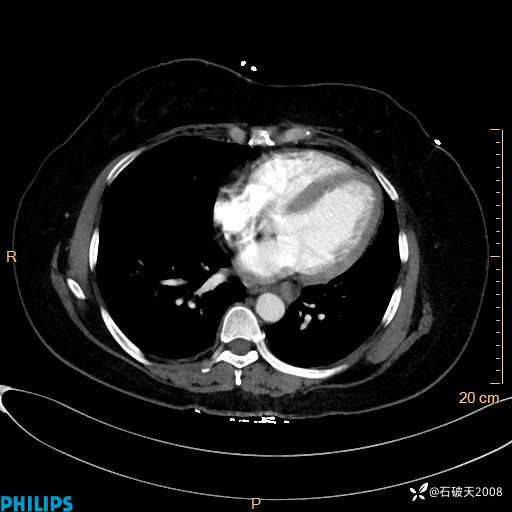

动脉期